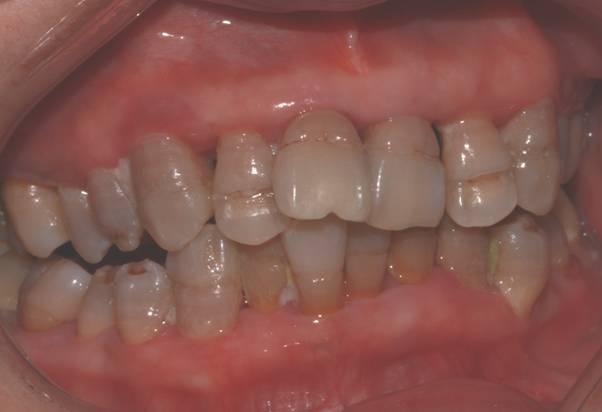

病例四:左图为修复前正面四环素牙,牙列不齐。中图为修复前侧面。右图为氧化锆修复后正面。

修复前侧面